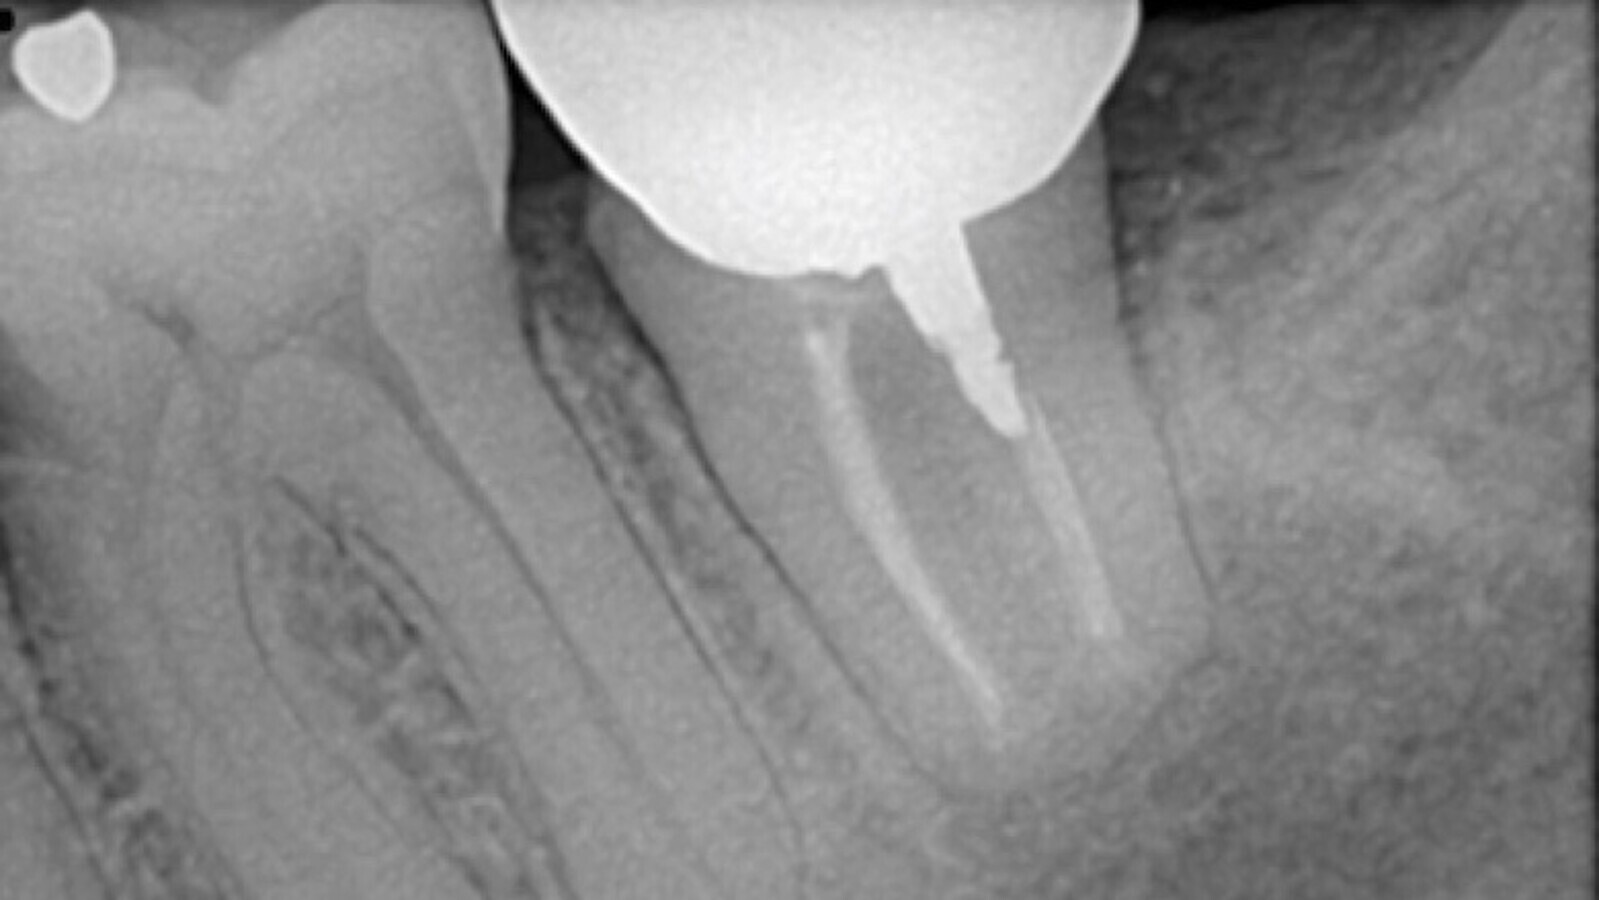

Figura 5. Control 1 año después del reimplante intencional.